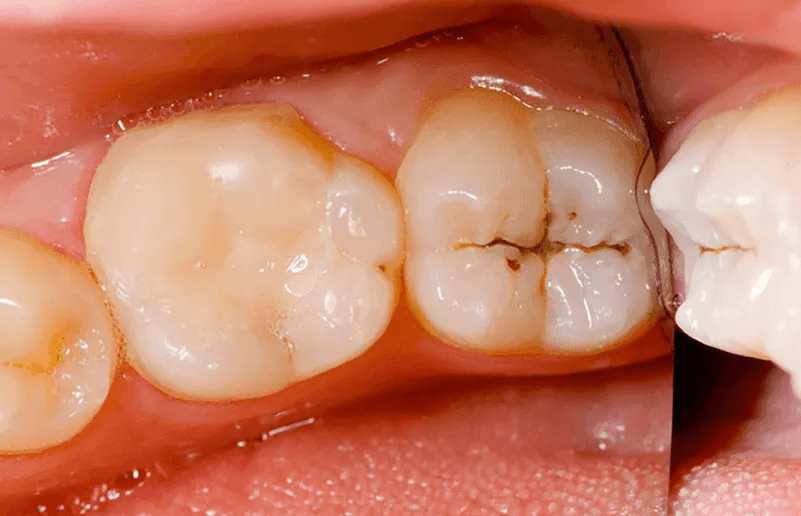

Cavities don’t appear overnight like a blister. They start when your tooth enamel—think of it as a honeycomb packed with minerals—loses those minerals to acidity. Foods, drinks, and even bacteria produce acids that dissolve the structure, creating tiny spaces. Plaque isn’t just “gunk.” It begins with harmful bacteria like Streptococcus mutans. Give them even a tiny bit of sugar—from soda, fruit, pastries, or natural sources—and they gain energy, stick to your teeth with sticky tendrils, multiply, and pump out more acid. This vicious cycle deepens the damage.

STOP—before you continue reading, take 30 seconds to assess your own sugar habits today. Quick mental exercise: Imagine your teeth as a fortress. Every sugary sip or snack is like handing the enemy a battering ram. But here’s what most people miss: Once minerals leach out, plaque sneaks in, and the infection (called caries) spreads. The visible hole? That’s just the collapse at the end. Self-check: On a scale of 1–5, how often do you experience that “off” feeling after eating sweets? If it’s a 3 or higher, this article is about to become your new best friend.